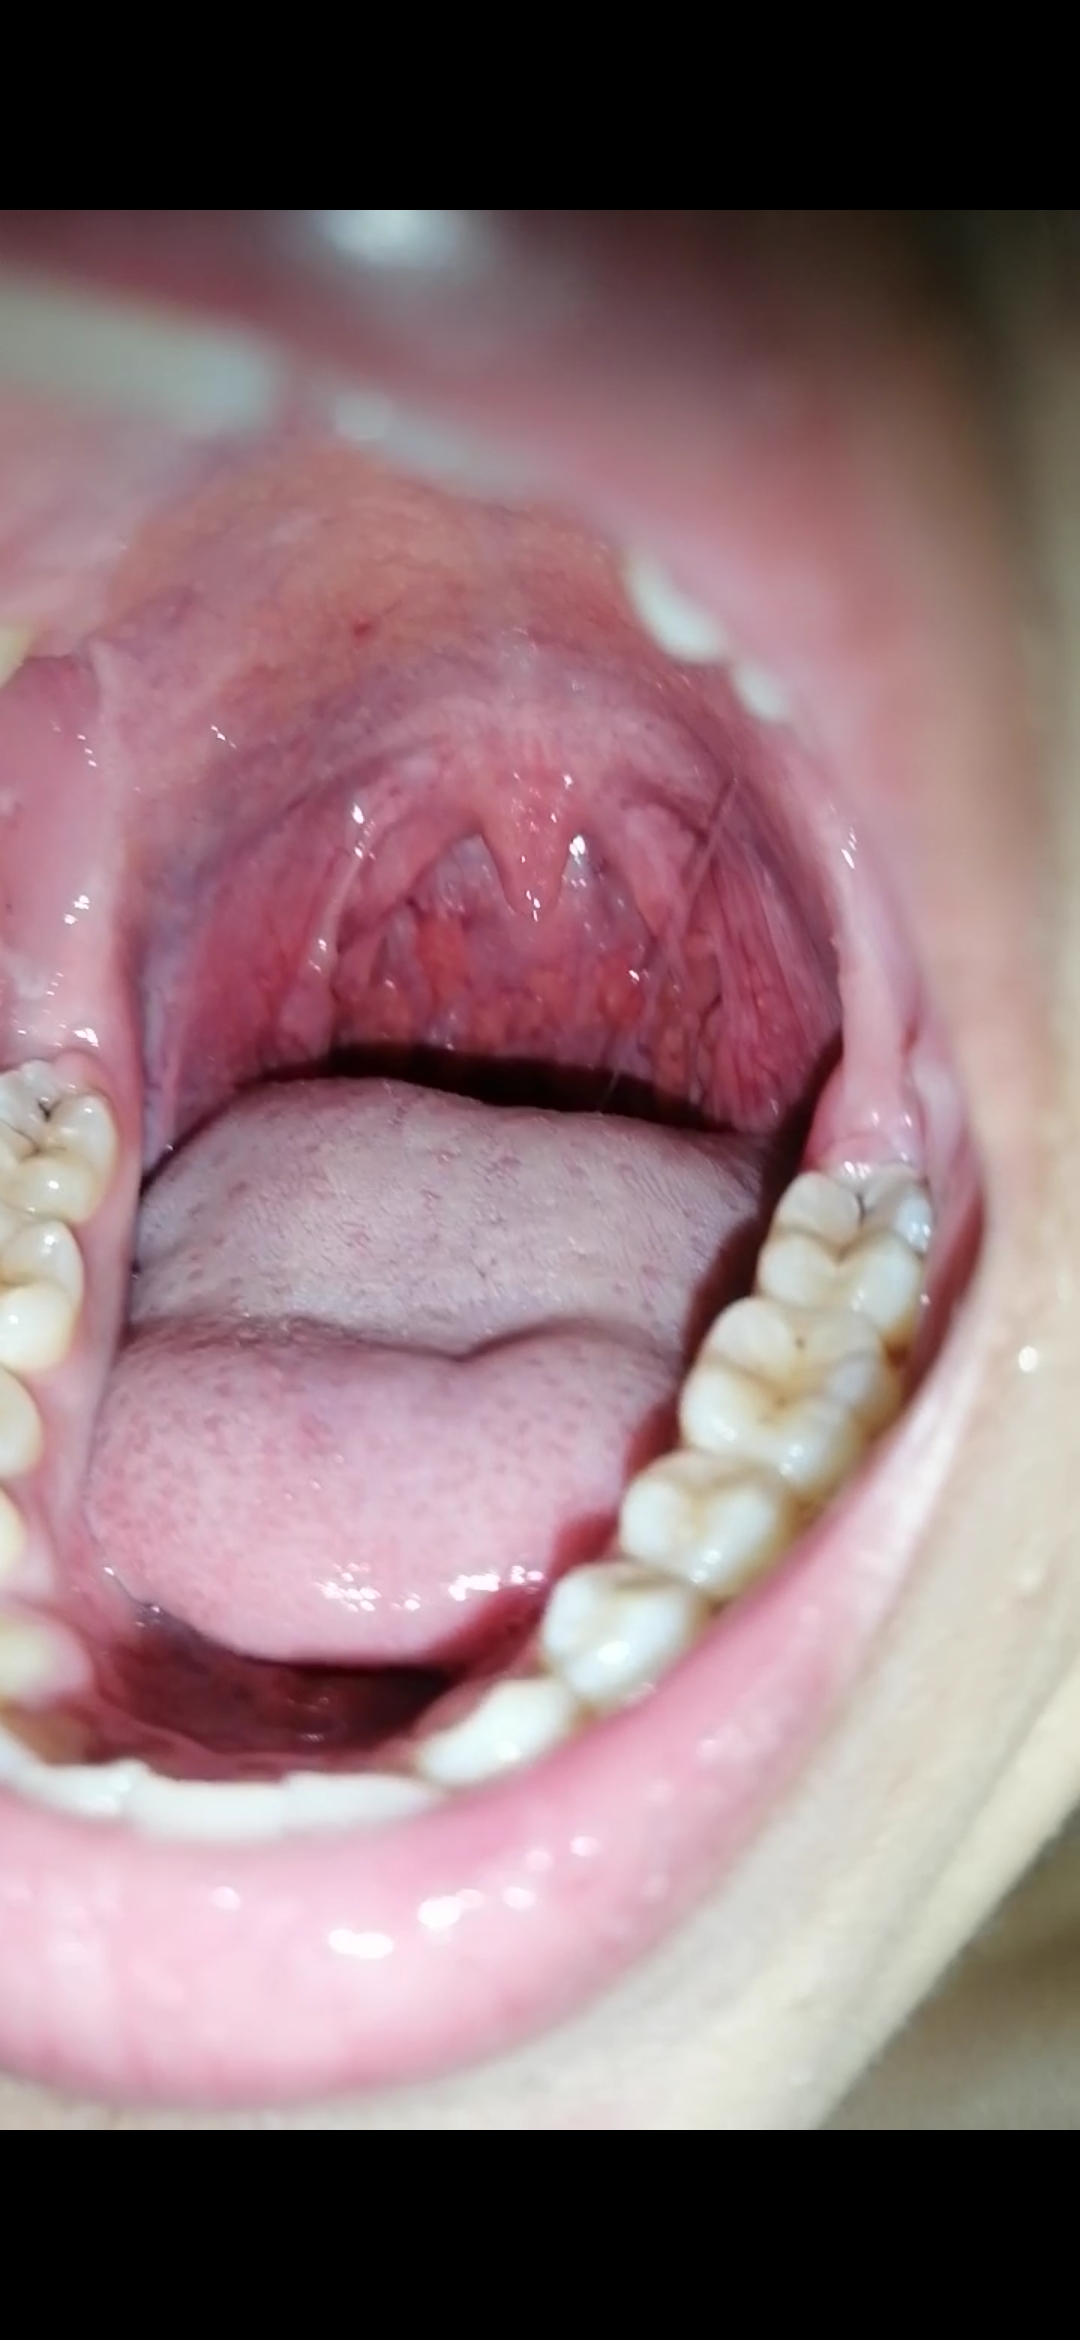

Hola asesor Enrique M ...comenze a salir con un chico y ya después tuvimos relaciones,  a los días me salieron como bultos en mi garganta amarillentos con bolas rojas en la lengua con tos y gripe, fui al medico me vio la garganta pero no me dijo nada, tengo 17 necesito saber si podría ser VIH, alguna ETS o otra infección menor